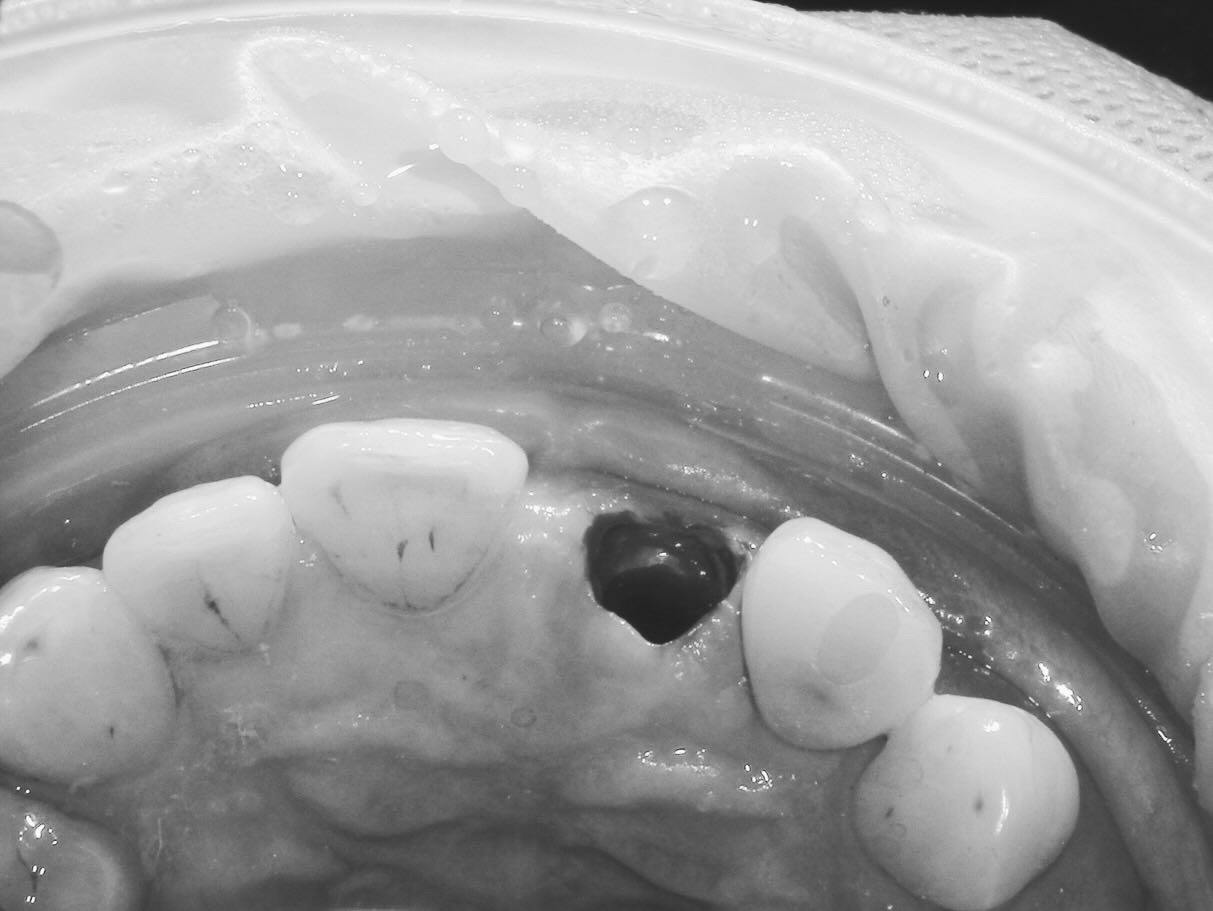

高精度感染根管治療

2024/11/16症例